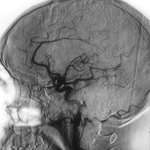

- Angiogram

An angiogram, also called an arteriogram, is an invasive diagnostic test that uses x-rays to take pictures of your blood vessels. A long flexible catheter is inserted through the blood stream to deliver dye (contrast agent) into the arteries making them visible on the x-ray. This test can help diagnose a stroke, aneurysm, arteriovenous malformation, tumor, clots, and arterial stenosis.